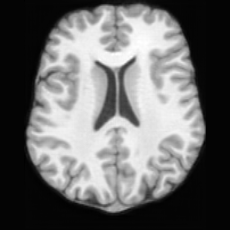

(a)PathologicalInput ImageSynthSR [18]Brain-ID [28]UNA [30]USBHealthyGround TruthRefer to captionRefer to captionRefer to captionRefer to captionRefer to captionRefer to captionRefer to captionRefer to captionRefer to captionRefer to captionRefer to captionRefer to captionRefer to captionRefer to captionRefer to captionRefer to captionRefer to captionRefer to captionRefer to captionRefer to captionRefer to captionRefer to captionRefer to captionRefer to caption(b)HealthyInput ImageConditionalLesion MaskUNA [30]USBRefer to captionRefer to captionRefer to captionRefer to captionRefer to captionRefer to captionRefer to captionRefer to captionRefer to captionRefer to captionRefer to captionRefer to captionRefer to captionRefer to captionRefer to captionRefer to caption

Figure 5: Comparison of bidirectional brain editing. (a) pathology-to-healthy, the circles and arrows highlight lesion regions and unsuccessful reconstructions; (b) healthy-to-pathology. Note that SynthSR and Brain-ID cannot perform healthy-to-pathology editing.

Pathology-to-Healthy Editing. Fig. 5 (a) presents comparison results on four input brain images with lesions of varying sizes, shapes, and densities. All competing models, although specialized for healthy brain image synthesis, struggle to reconstruct pathological regions, especially near lesion boundaries. In contrast, USB accurately reconstructs the corresponding healthy brain, even in challenging cases with large, high-density lesions where normal brain structures are almost completely obscured (last row). Tab. 2 provides a quantitative comparison for pathology-to-healthy editing, where USB achieves the best performance across all three datasets, demonstrating the effectiveness of its unified framework in reconstructing healthy brains from pathological inputs. Additional results are in Suppl. B.